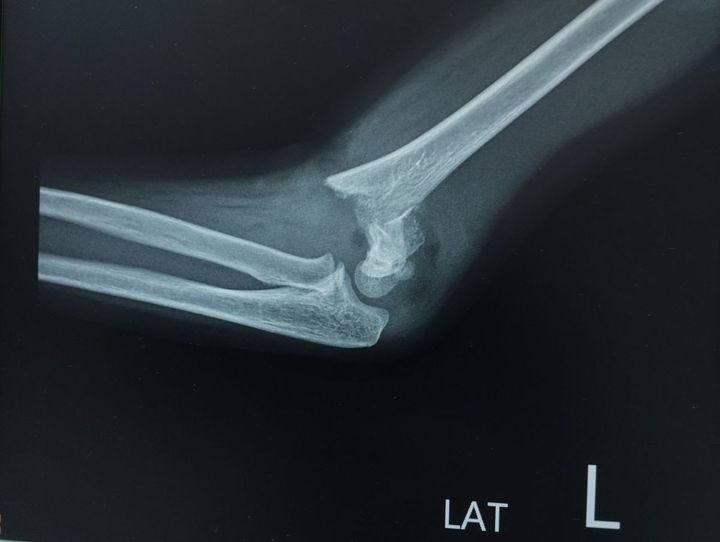

「実は私、2022年は6月に転んで左肘を骨折してしまい、当時はまだ週3回リハビリ中だったのです。なので、いつも帰省は車でしたが、新幹線を使いました」

左肘のレントゲン写真

※写真はイメージです